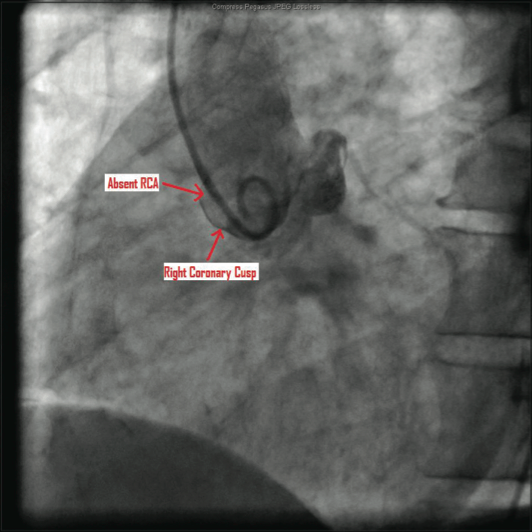

The catheterization and angiogram showed a patent left main coronary artery that bifurcated into the left anterior descending (LAD) and the left circumflex (LCX). The LAD had a mid 50% stenosis and the LCX was a large-sized vessel that gave off three obtuse marginal (OM) branches and continued distally into the right

side of the heart, filling the right coronary artery (RCA) from the distal end retrograde. The LCX had a mid 70-80% lesion that was confirmed by intravascular ultrasound (IVUS). The right coronary artery had no ostium and received retrograde filling via the LCX, continuing distally into the right myocardium. The LCX 80% mid stenosis was successfully revascularized with deployment of two drug-eluting stents. The patient was placed on post-procedure clopidogrel, simvastatin, beta blockers, and nitroglycerin.